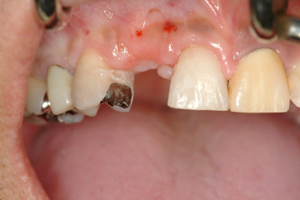

前歯の差し歯が折れて

抜歯した症例です

どの歯がインプラントかわかりません。

特に前歯のインプラントは審美性が

求められるので、

繊細な技術が必要です。